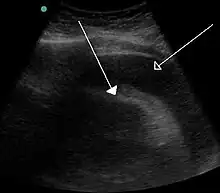

A very large pericardial effusion resulting in tamponade as a result of bleeding from cancer as seen on ultrasound. Closed arrow – the heart; open arrow – the effusion